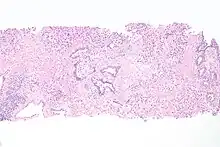

Histopathology of urothelial carcinoma of the urinary bladder, showing a nested pattern of invasion. Transurethral biopsy. H&E stain

Histopathology of urothelial carcinoma of the urinary bladder.